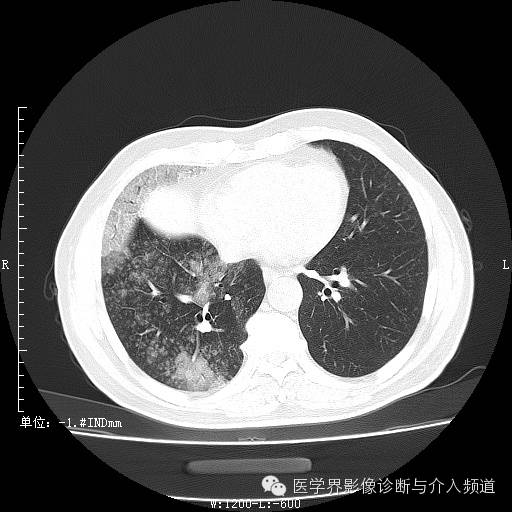

二次复查

二次复查:双肺多发实变、磨玻璃结构及粟粒结节,较前病变范围明显增大右侧并发气胸。